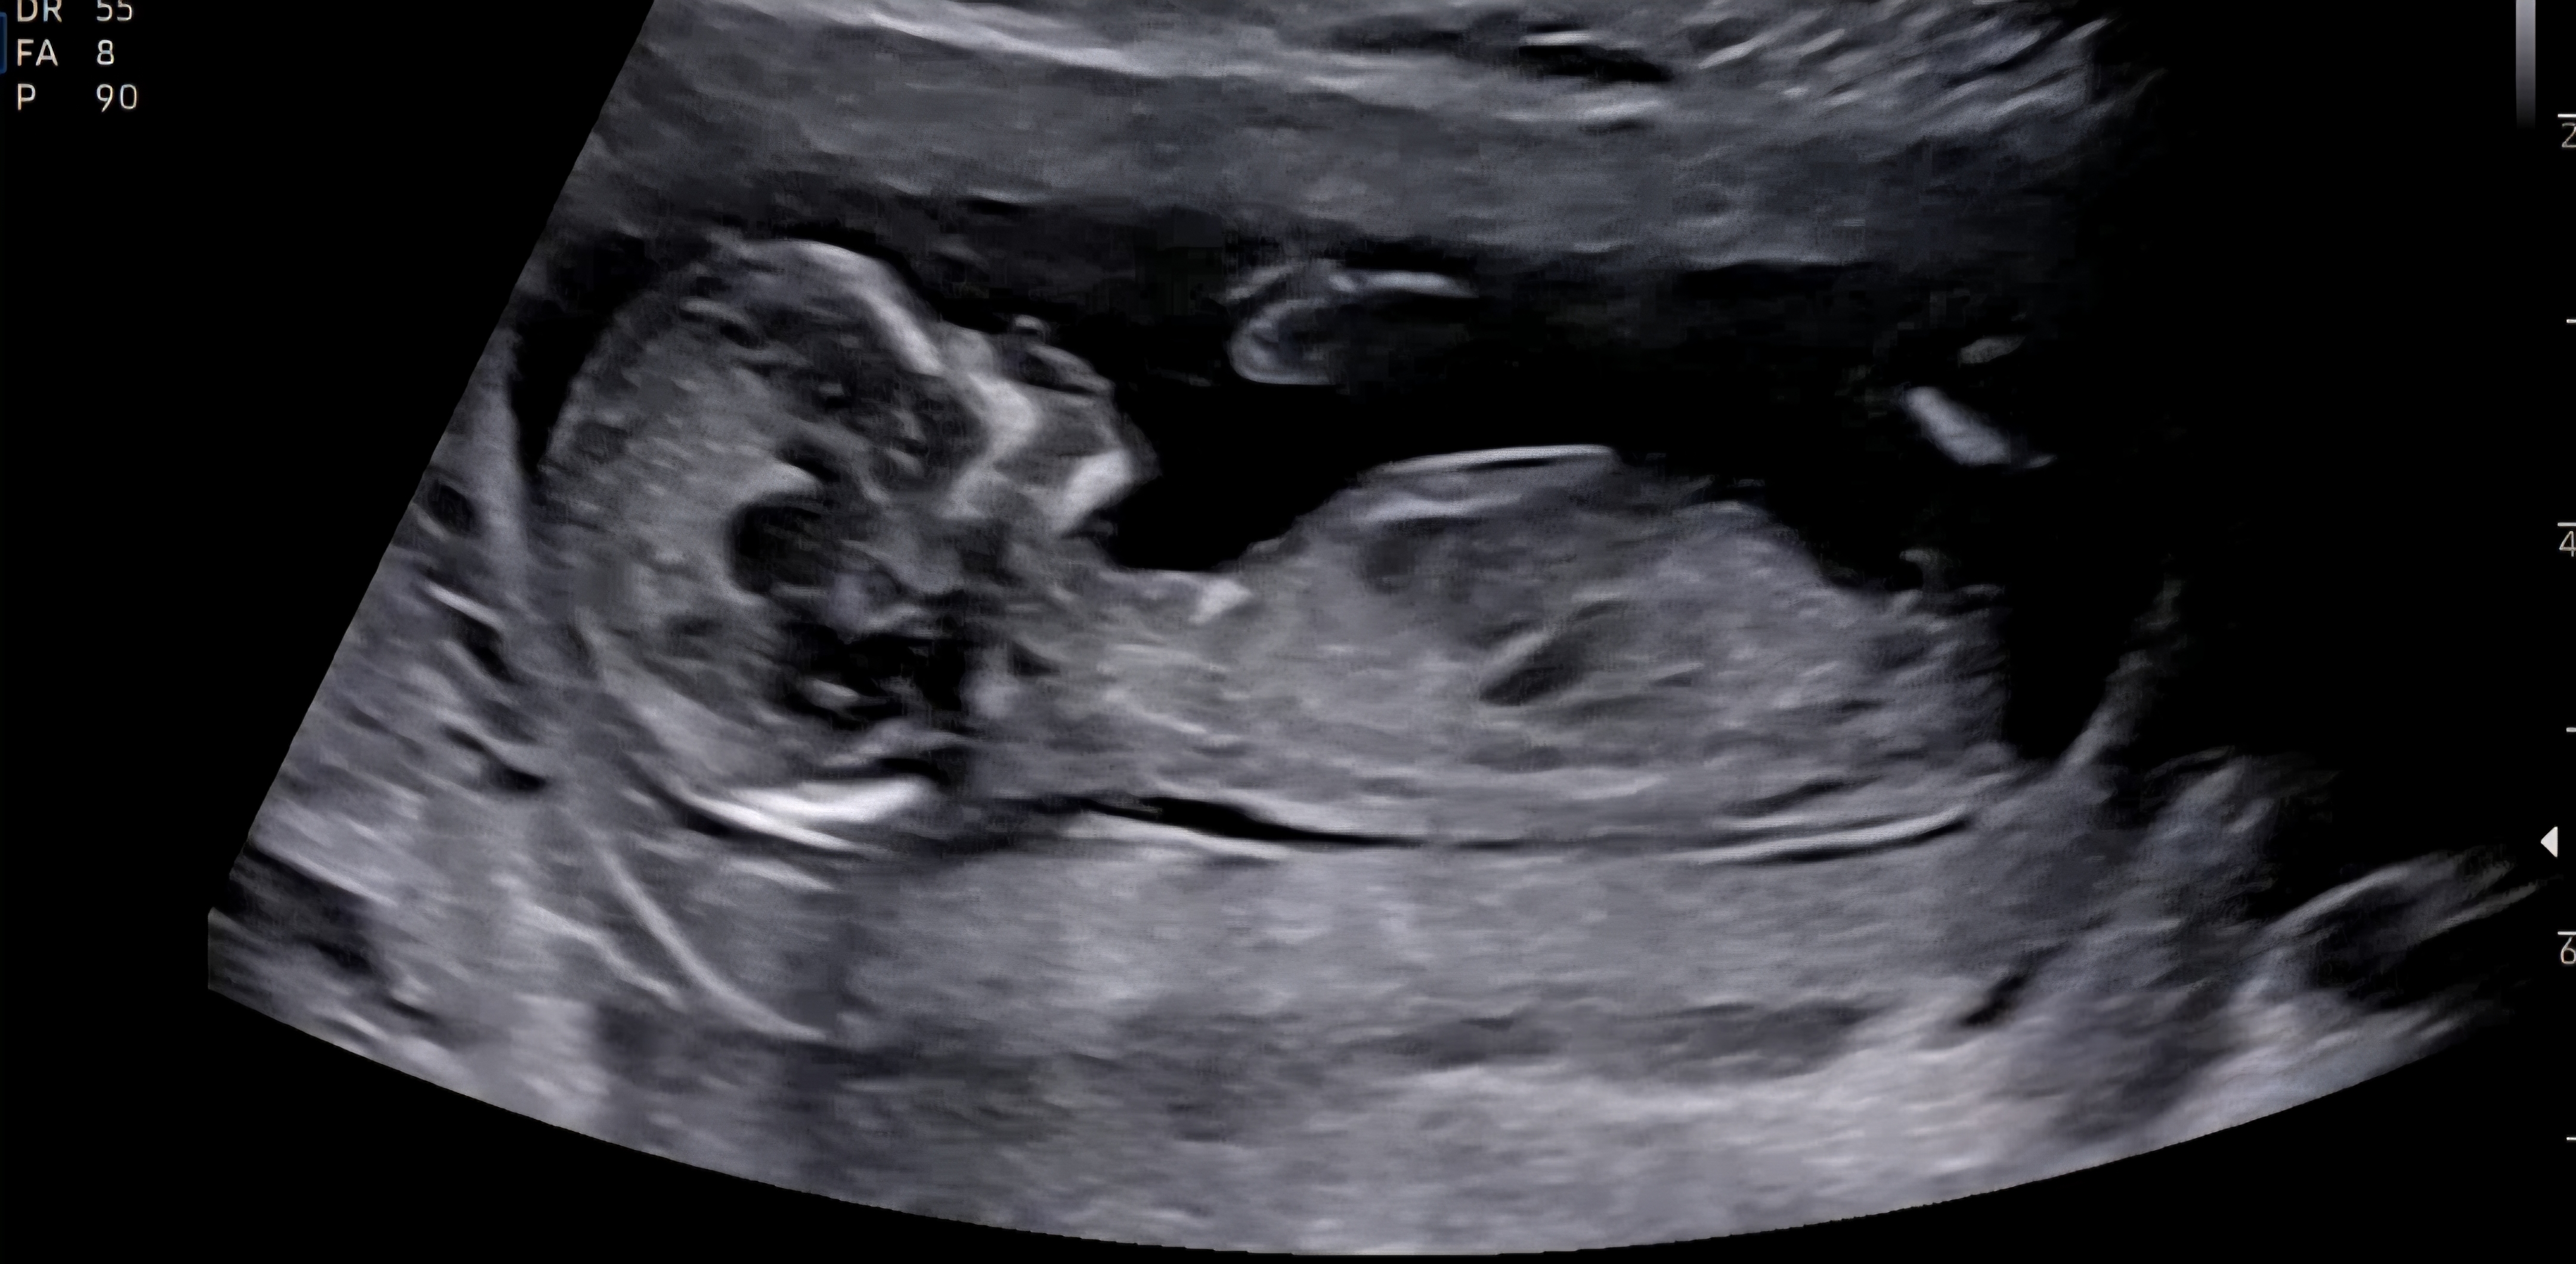

12주차 기형아검사 하구왔어요. 무사통과해서 기뻐요.. ㅎㅎ 옆모습이 요 사진 뿐인데 혹시 각도법으로 성별 보이시는 분 계신가요?